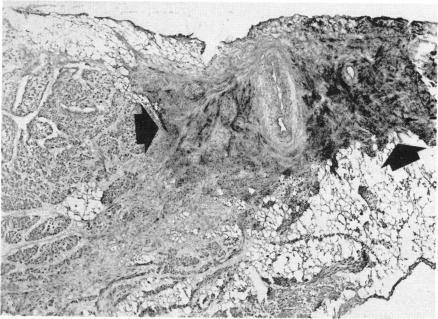

Cardiac innervation: anatomic and pharmacologic relations.

Bull N Y Acad Med. 1967 Dec;43(12):1041-86.